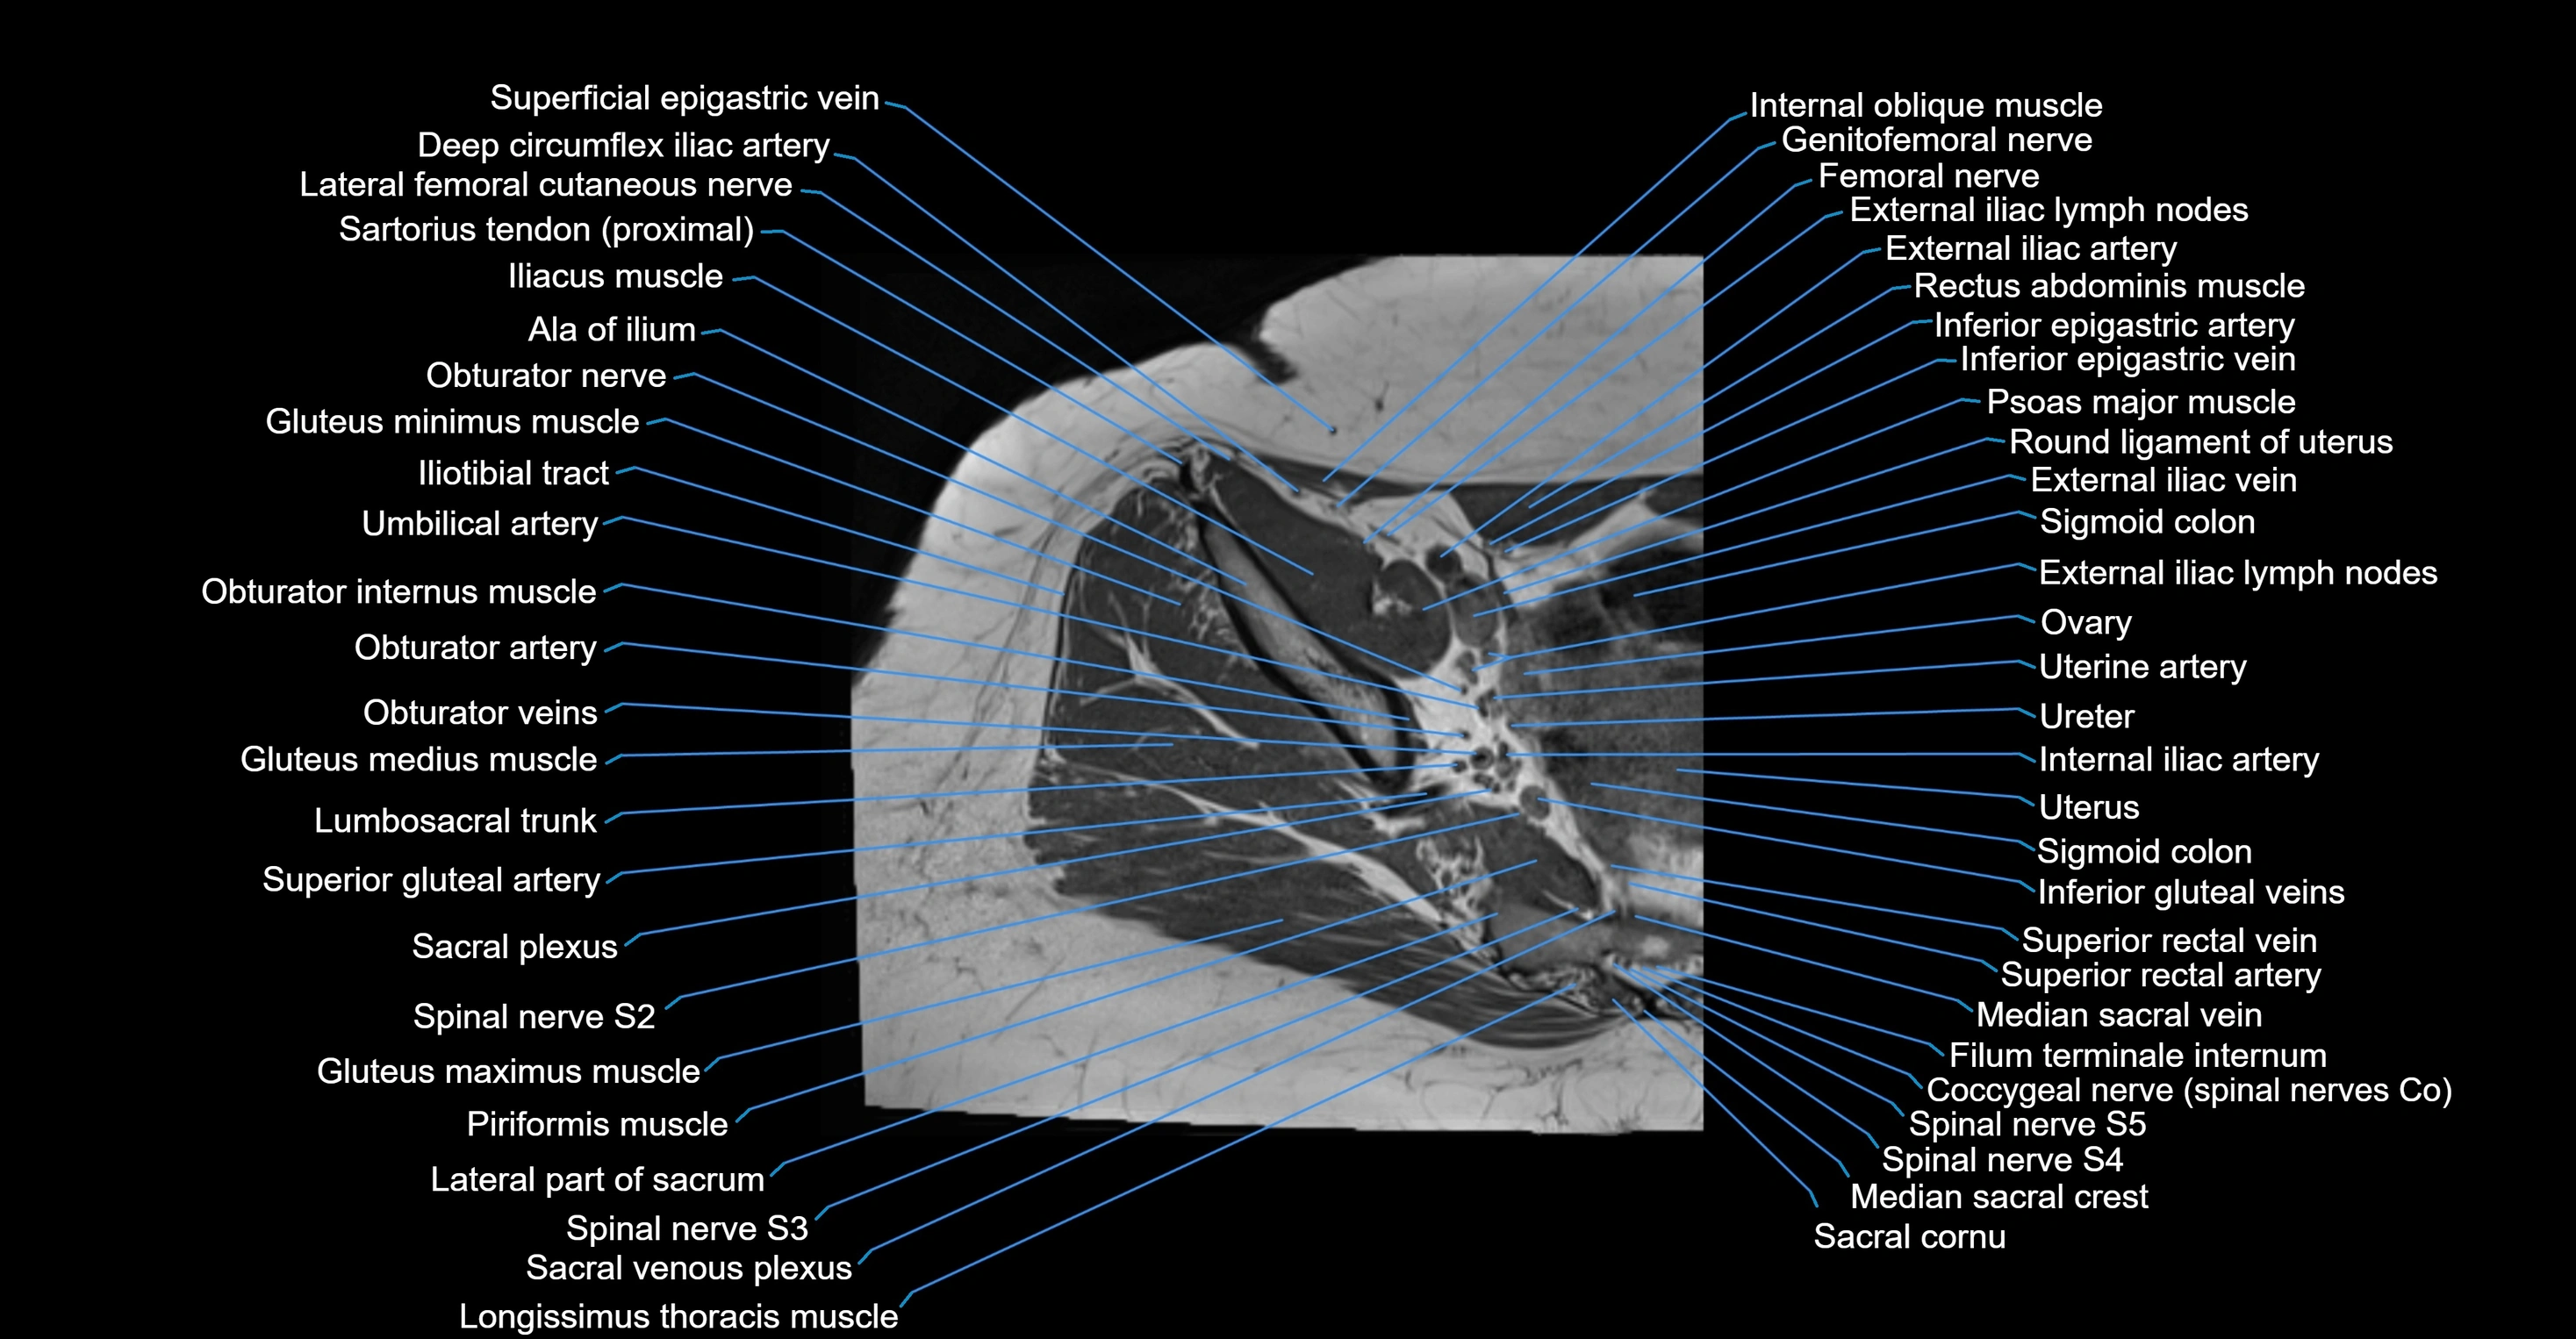

- Ala of ilium (wing of ilium)

- Deep circumflex iliac artery

- External iliac artery

- External iliac lymph nodes

- External iliac vein

- Femoral nerve

- Filum terminale internum

- Genitofemoral nerve

- Gluteus maximus muscle

- Gluteus medius muscle

- Gluteus minimus muscle

- Iliotibial tract

- Inferior epigastric artery

- Inferior epigastric veins

- Internal iliac artery

- Lumbosacral trunk

- Median sacral vein

- Median umbilical ligament

- Obturator artery

- Obturator internus muscle

- Obturator internus tendon

- Ovaries

- Round ligament of uterus

- Sacral plexus

- Sigmoid colon

- Spinal nerve S1

- Spinal nerve S2

- Spinal nerve S3

- Spinal nerve S4

- Spinal nerve S5

- Superior gluteal artery

- Superior rectal vein

- Umbilical artery

- Uterus